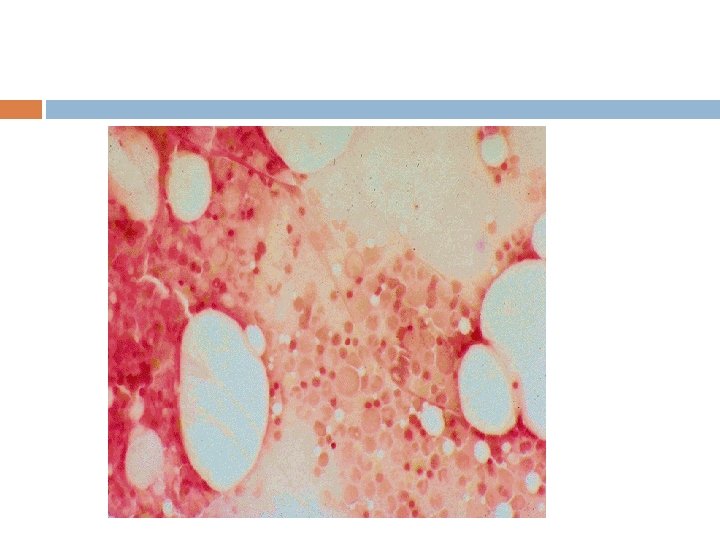

MEGALOBLASTİK ANEMİ DNA sentez bozukluğu nedeni ile kemik iliğinde hematopoetik hücreler yanlış yapılır. Çekirdek gelişmesi gecikirken, sitoplazma büyümeye devam eder (nükleer-sitoplazmik uyumsuzluk). Bu hücrelerdeki yanlış gelişme (displazi) hem hücre fonksiyonlarını bozar, hem de bunların kemik iliğinde ölmesinde ve periferik kana çıkamamasına yol açar (pansitopeni) Bu nedenle kemik iliği hipersellüler iken periferik kanda pansitopeni vardır (ineffektif eritropoez) Kemik iliğindeki aşırı hücre yıkımı nedeni ile, Hiperbilirübinemi (indirekt) LDH yüksekliği izlenir

LAB Periferik yaymada makroovalositoz Periferik yaymada hipersegmente nötrofiller Kemik iliğinde belirgin hipersellülarite, megaloblastik değişiklikler Serum Kobalamin düzeyi çok düşer: <100 pg/ml (200700) Hastaların 2/3’ünde dolaşan IF antikorlar Gastrin düzeyinde artma Schilling testi (Radyoişaretli B 12 emilim testi)